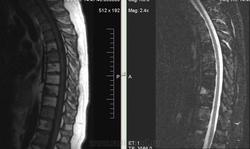

Коллеги, подскажите, пожалуйста, а как оценивать такие изменения? Из той же "оперы"? Женщина, 1966г.р., жалуется на выраженные боли в пояснице и левой ноге после умеренных нагрузок.

Здесь я особых проблем с крестцово-подвздошными сочленениями не вижу.